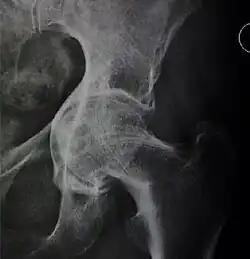

![Figure 5 (c). Protrusio acetabuli.[3]](./X-ray_of_protrusio_acetabuli.jpg)